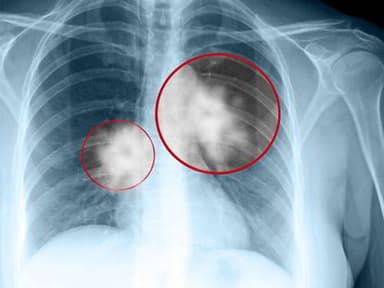

U phổi là sự phát triển bất thường của các tế bào tại phổi. Với u ác tính (ung thư phổi), các tế bào này còn có thể di căn đến hạch, cơ quan lân cận và ở xa, đe dọa trực tiếp đến tính mạng người bệnh.